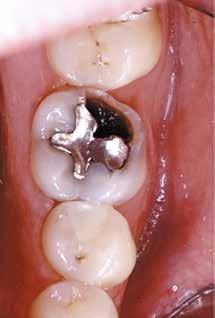

En dybtliggende amalgam-misfarvning udgør en af de mest vanskelige udfordringer ved udskiftning af restaureringer. Transcend Universal Body farven blev anvendt til at erstatte amalgamen, uden brug af blokeringsmateriale. Bemærk, hvor fremragende farven blender ind i den bevarede crista obliqua.

Før Efter